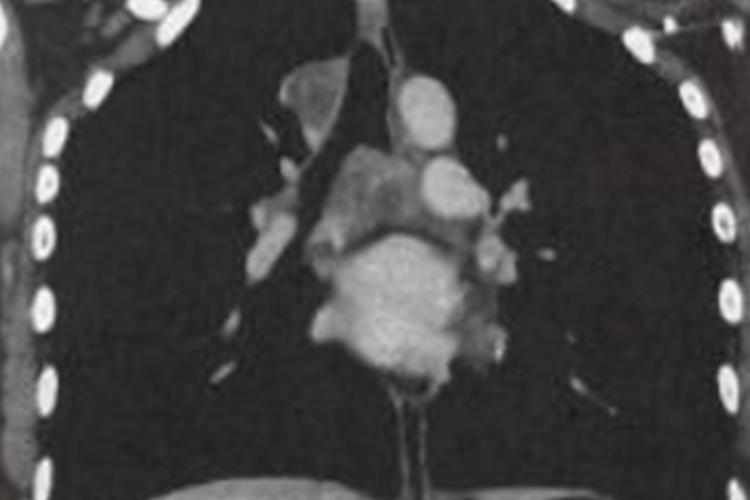

可见原发浸润灶,多位于中上肺野,呈圆形、类圆形或局限性斑片影。还可见自原发病灶向肺门走行的不规则条索状影、肺门影增大或纵隔淋巴结增大。

分为急性、亚急性和慢性血行播散型肺结核,急性表现为两肺弥漫分布的粟粒状影,粟粒大小为1-3mm,边缘较清晰。典型表现为“三均匀”,即分布均匀、大小均匀和密度均匀。亚急性、慢性表现为双肺上、中叶粟粒状或较粟粒更大的小结节影,其大小不一、密度不等、分布不均,即“三不均匀”,肺尖部及锁骨下病灶可为硬结、钙化及纤维化,而其余病灶呈增殖或渗出性改变。

干酪为主型:表现为上肺大叶性实变,其内可见多个小空洞,下肺常可见沿支气管分布的播散病灶。结核球呈圆形或类圆形,多数密度不均,其内常可见钙化,有时可见小空洞影,边缘清楚,部分可呈浅分叶状,少数可见毛刺征或胸膜凹陷征,周围常可见卫星病灶。